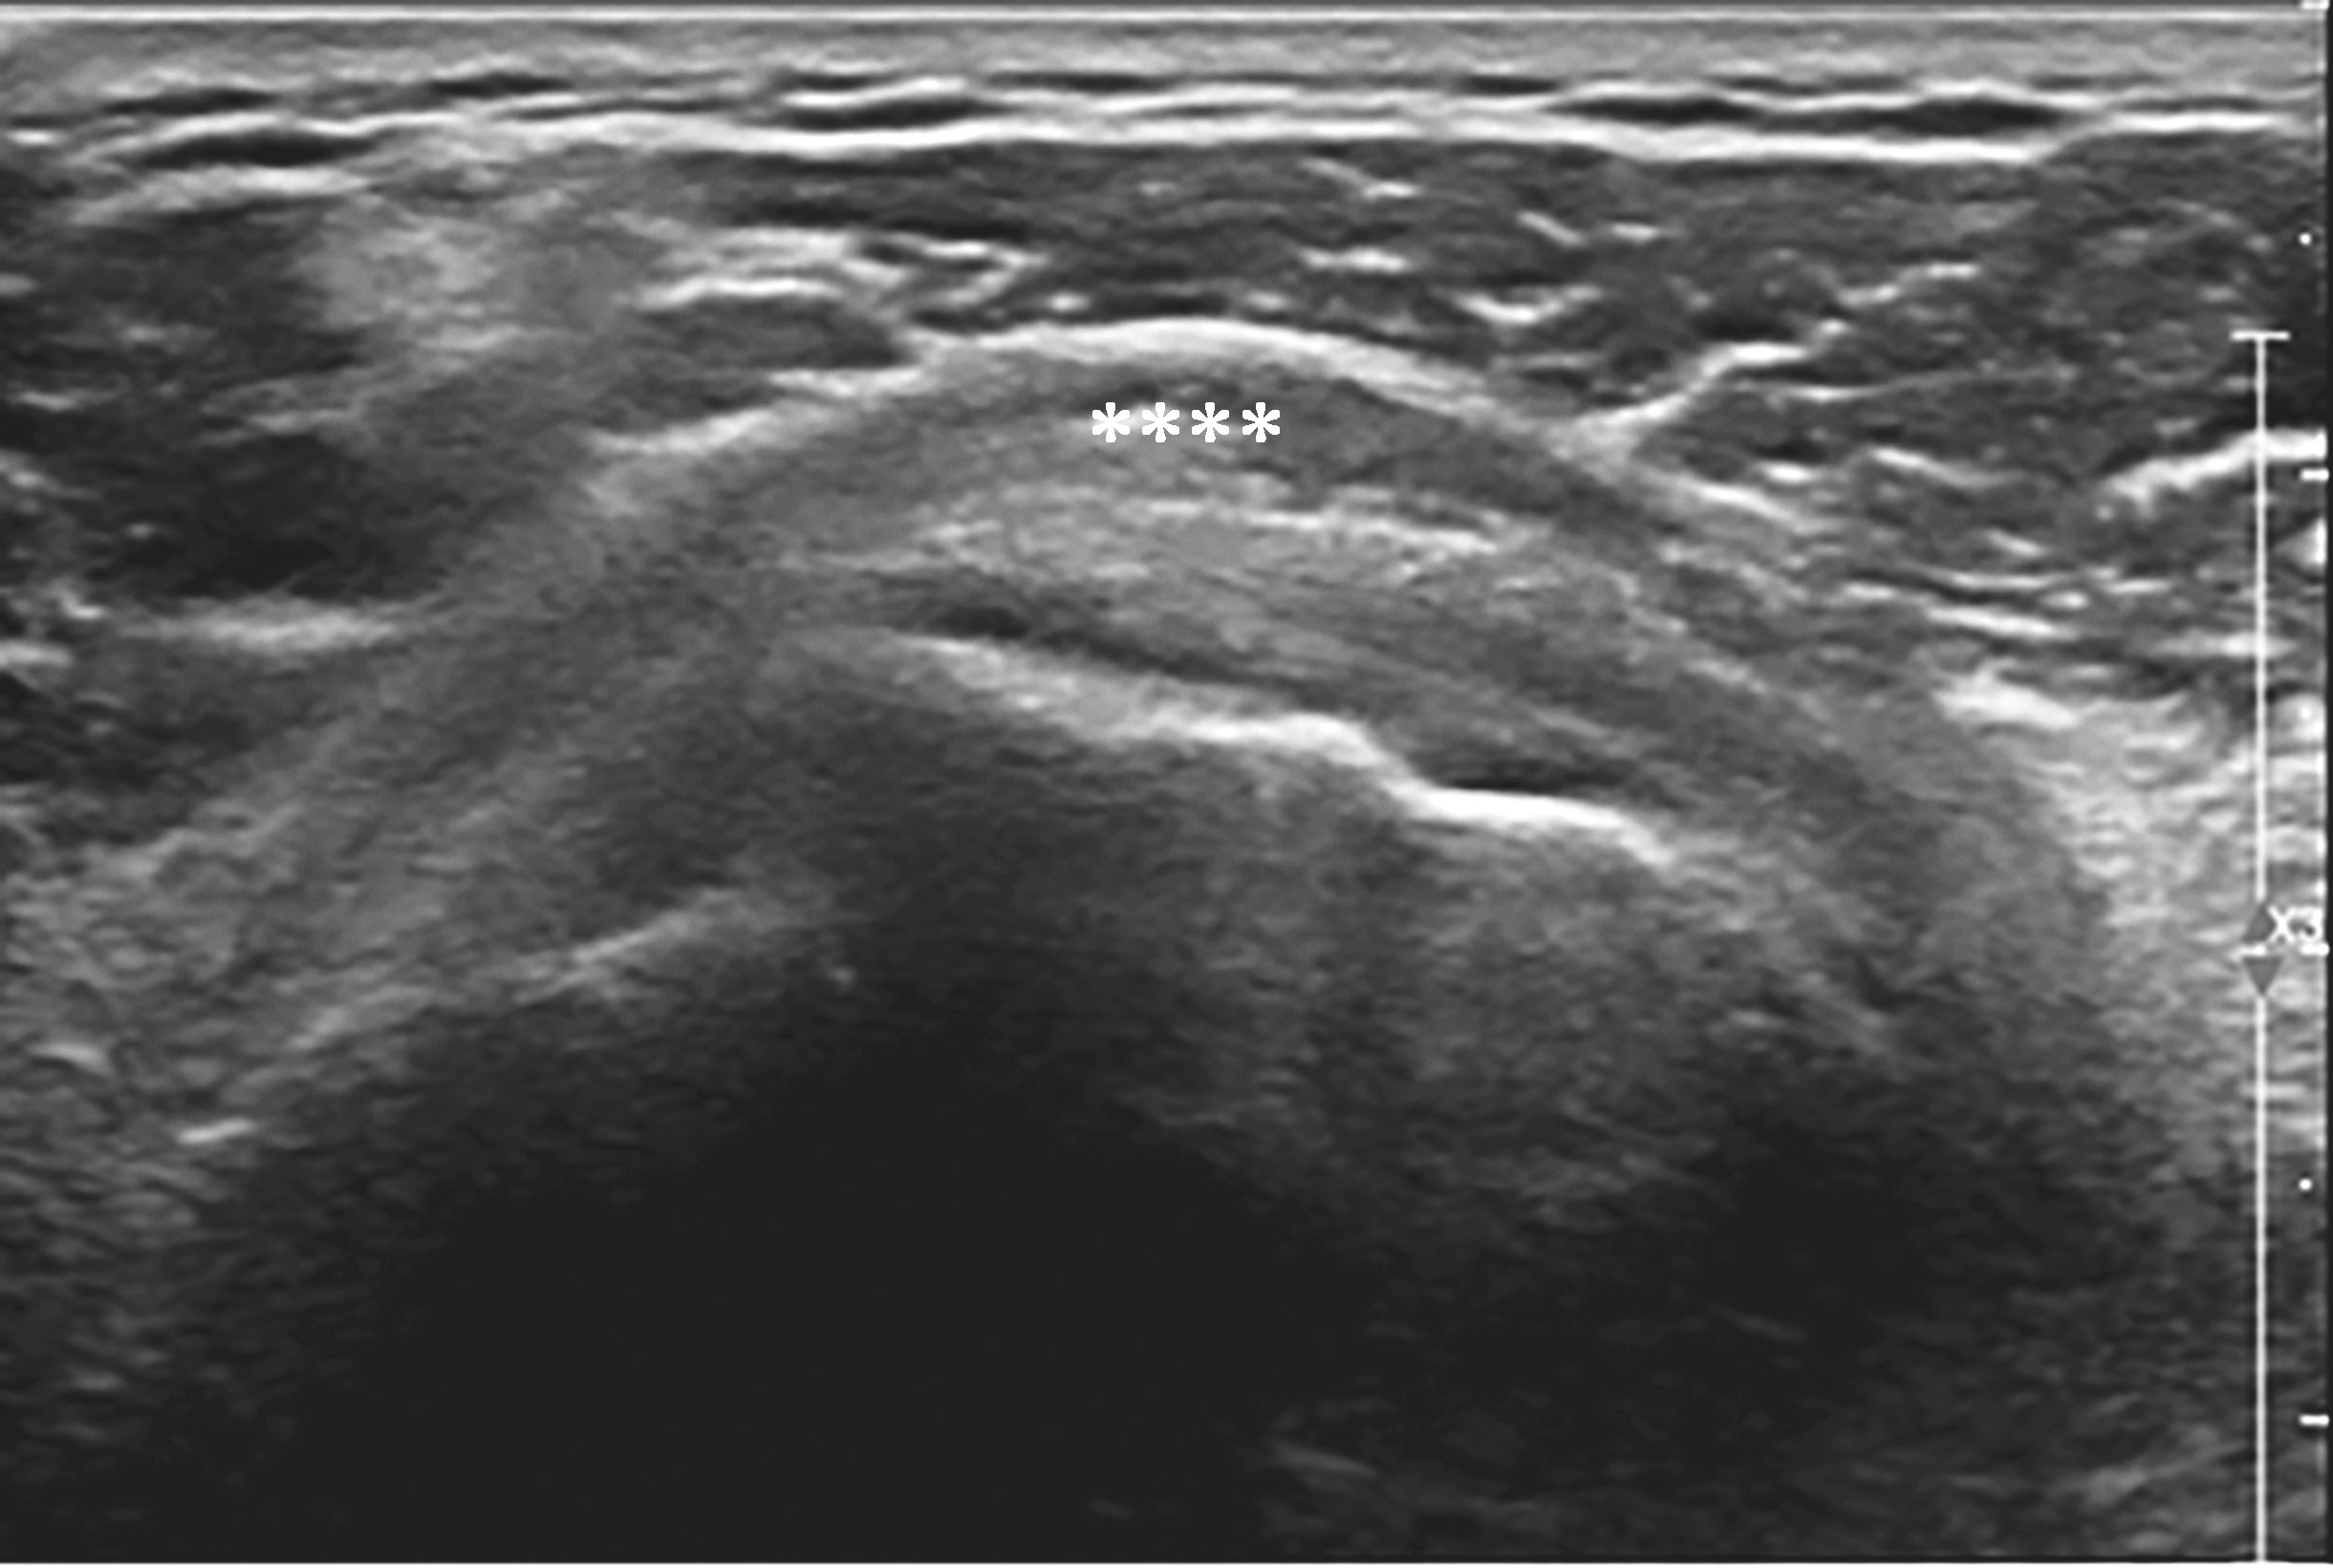

2.当针尖进入滑囊后(图2-1-5),可推注少量药物,若推注顺利可观察到滑囊扩张及药物的弥散(图2-1-6),同时也表明针尖准确位于滑囊内,可继续推注混合药物3~5ml。若推注受阻,原因有可能是针尖在滑囊组织内,需重新调整针尖,也可能是滑囊内粘连明显所致,可加大力度,利用液体推注的压力松解粘连,松解后可见粘连带呈线状稍强回声(图2-1-7),也可在粘连远端重新选择部位注入药物,这类患者可能需要多次治疗才能达到较好的疗效。

▲ 图2-1-5 超声引导下肩峰下-三角肌下滑囊穿刺治疗超声图

箭头:显示穿刺针尖进入滑囊;星号:冈上肌腱;H:肱骨头

▲ 图2-1-6 肩峰下-三角肌下滑囊穿刺治疗后超声图

星号:药物注射后在滑囊内均匀弥散;H:肱骨